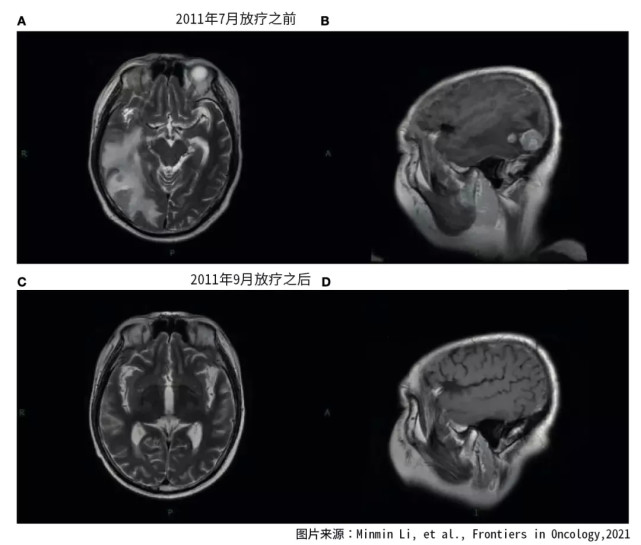

图片图1. 2011年7月-9月放疗前后脑核磁检查结果

2011年7月,患者因为脑部转移瘤复发而入院,患者表现为意识障碍。PET-CT扫描显示脑外的肿瘤病灶稳定。

图片图2. 2016年1月脑放疗之前的核磁结果

患者每天使用150毫克的厄洛替尼进行治疗,同时使用三维放射治疗,再次进行了全脑放射治疗。总剂量为30个格瑞,分15次完成。放疗完成之后,患者进行了四个周期的尼莫司汀和厄洛替尼的维持治疗。2011年9月,脑部核磁发现转移灶显著缩小,患者的病情得到了有效控制。